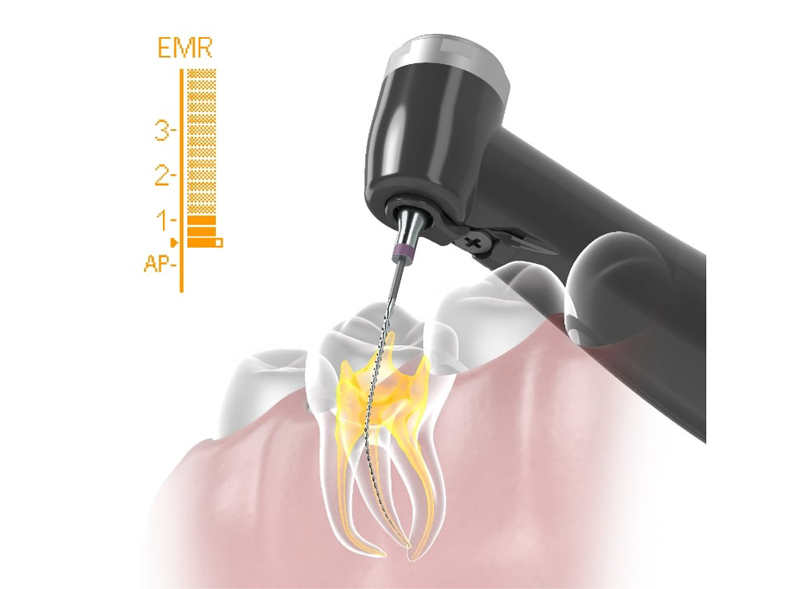

POINT治療の成功率を支えるニッケルチタンファイル・根管長測定器

従来のステンレス製ファイルは硬度が高いため、大きく湾曲していたり、狭くなっていたりする難易度の高い根管では、歯の組織を過剰に削ってしまうリスクがありました。

それに対し、当院で採用しているニッケルチタンファイルは、形状記憶特性と優れた柔軟性を併せ持ちます。この特性により、複雑な根管の形状に沿ってしなやかに進み、歯質へのダメージを最小限に抑えながら、根の先端隅々まで感染源を精密に除去することが可能です。

また、専用の根管拡大装置に装着して使用することで、治療の効率と精度が向上し、患者様の負担軽減や治療時間の短縮にも繋がります。